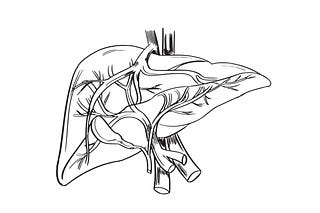

Fístula arterio-portal congénita en una gata

Póster sobre esta interesante anomalía vascular hepática en una gata